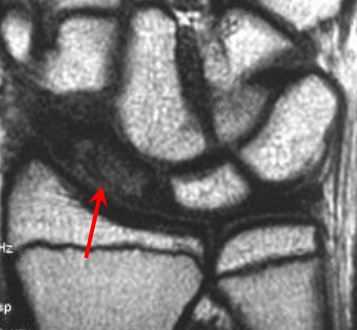

МРТ кисти. Т1-взвешенная корональная МРТ. Асептический некроз ладьевидной кости.

На асептический некроз (болезнь Кинбека, Kienböck) очень похож синдром локтевого вклинения, когда ладьевидная кость вклинивается в локтевую. МРТ мелких суставов кисти обсуждается в отдельной статье.